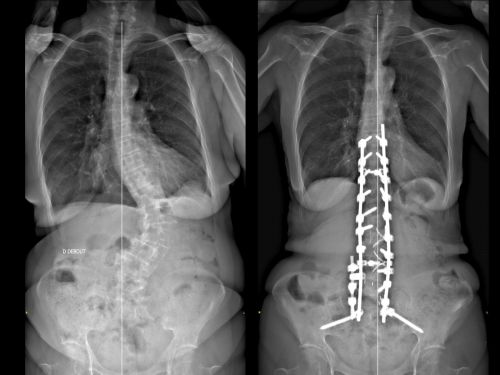

Différents types de traitements chirurgicaux existent. Il peut s’agir d’une chirurgie réalisée par voie postérieure ou antérieure, mais également dans certaines situations par la combinaison de ces abords. Les procédures chirurgicales ont progressé en matière de sécurité au bloc opératoire. Ce type de procédure nécessite l’utilisation de techniques spécifiques dédiées telles que le neuro-monitoring per opératoire, et/ou la neuronavigation.

- Correction de la déformation : Mise en place d’une instrumentation (ostéosynthèse rachidienne) qui permet de réduire la déformation dans les 3 plans de l’espace.

- Libération des structures nerveuses : Par une décompression directe ou indirecte des racines nerveuses.

- Fusionner les vertèbres : Réalisation d’une arthrodèse avec la mise en place de greffons osseux permettant d’obtenir une fusion osseuse entre les vertèbres afin de renforcer l’ostéosynthèse réalisée et de consolider le résultat à long terme. Cette fusion peut nécessiter la mise en place de cage (par voie antérieure et/ou postérieure), entre les vertèbres, au niveau des disques intervertébraux.